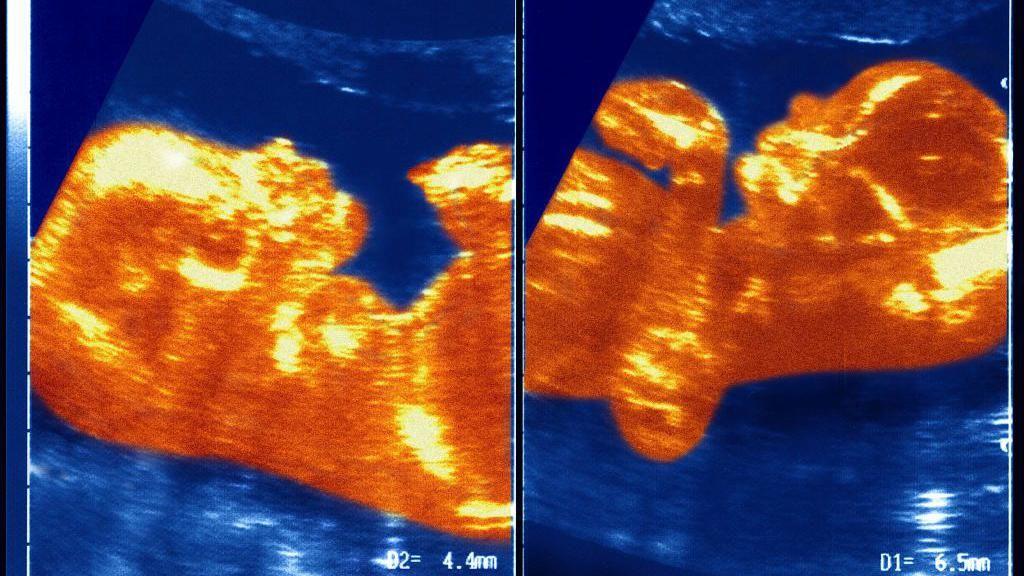

Naučnici pretpostavljaju da su u materici placente Ane Paule i njenog brata blizanca ostvarile neku vrstu kontakta, čime je obrazovana veza između krvnih sudova koji su prenosili krv dečaka u devojčicu.

„Došlo je do transfuzije krvi koju nazivamo sindrom međublizanačke transfuzije.

„U jednom trenutku, vene i arterije blizanaca su se isprepletale u pupčanoj vrpci i on je sav njegov krvni materijal preneo Ane Paule", objašnjava profesor Masijel.